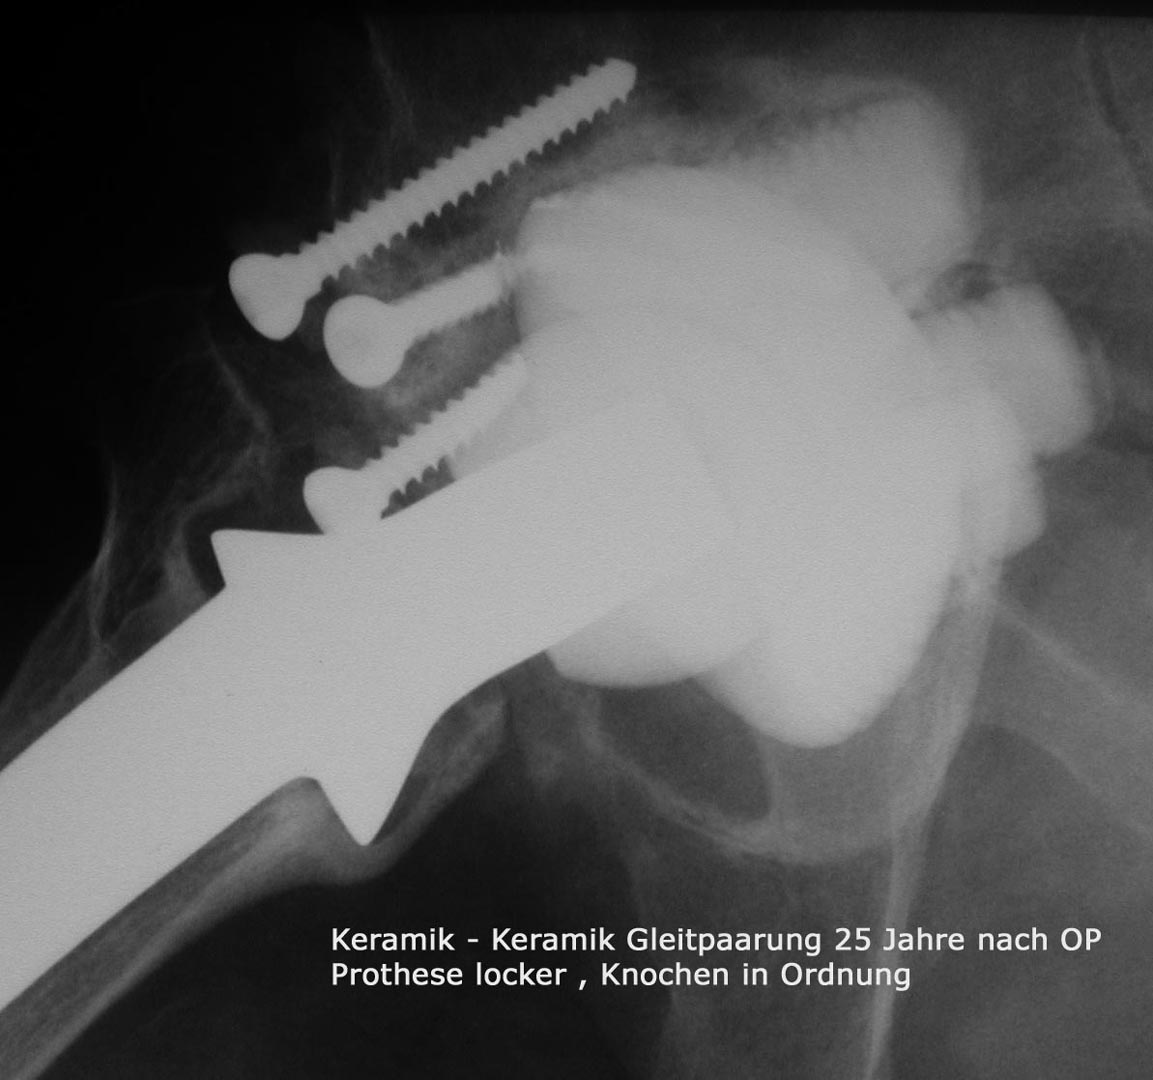

Die Hüftoperation bei Abnützungserkrankungen des Hüftgelenks wird in der übergrossen Anzahl der Fälle mit sogenannten zementfreien Prothesen durchgeführt , was bedeutet , dass die beiden Prothesenteile, also Pfanne und Schaft direkt in  Hüft und Oberschenkelknochen verankert werden können.

Dies ist zum einen durch passgenaue Fräsvorgänge der Knochen und zum anderen durch besondere Merkmale der Prothesenform selbst und der Oberflächen der Prothesen möglich. In Kombination mit der Keramik/Keramik Eigenpaarung , die für eine grosse Verschleißfestigkeit schon über Jahrzehnte bekannt ist ( siehe eigene Publikationen – Wissenschaftliche Tätigkeit) ist damit eine dauerhafte,stabile Verankerung und eine gute Funtion gewährleistet.